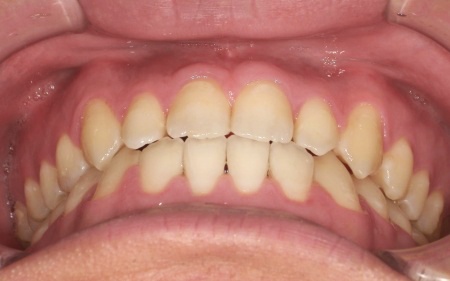

20代男性 受け口のように見える切端咬合をセラミックブラケットによる矯正治療で改善した症例

拝見したところ、上下前歯の先端同士が触れ合う「切端咬合(せったんこうごう)」の状態でした。

通常は上前歯が下前歯をわずかに覆うように重なりますが、患者様の場合は上下前歯の先端がほぼ同じ高さで噛み合っているため、受け口のような印象がみられました。

最後に、歯並びと噛み合わせが整い、見た目にも問題がないことを確認し、治療を終了しています。